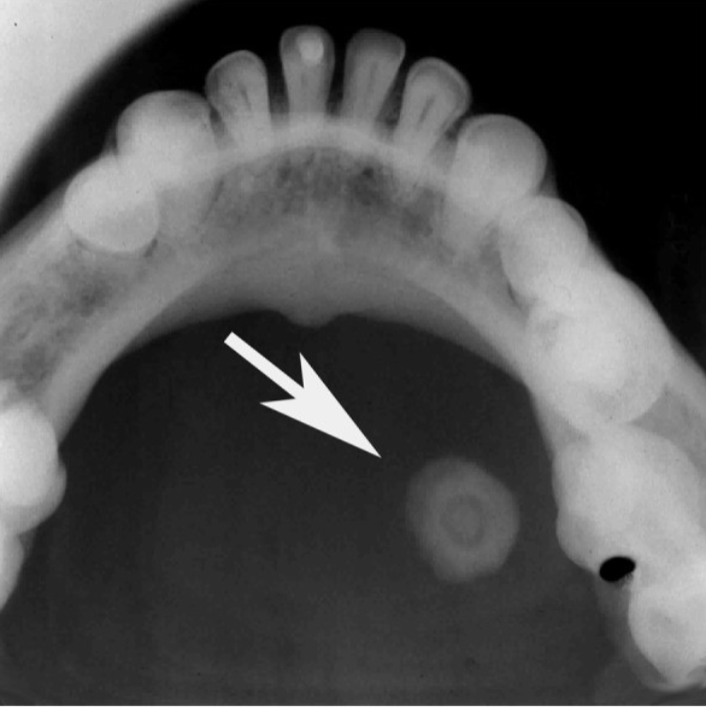

Purpose of localization

foreign bodies, impacted, unerupted teeth, retained roots, root positions, salivary stones, jaw fractures, broken needles and instruments, restorative materials

right angle technique